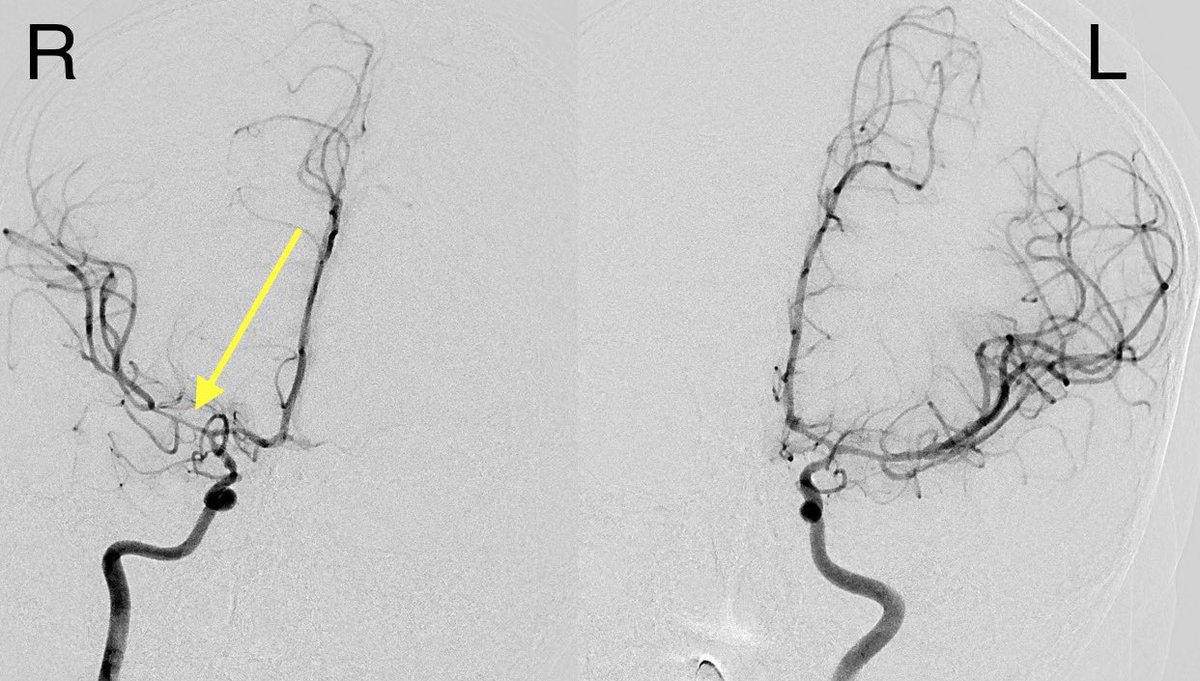

▶️CTA: Severe spasm of right ICA terminus and MCA and to a lesser degree, the left side as well

▶️Spasm was confirmed on angio in the right ICA terminus and MCA (greater than left) …treated with verapamil